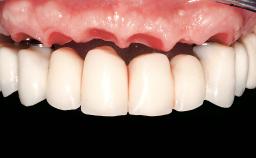

Immediate Loading of Eight Implants in the Maxilla and Six Implants in the Mandible and Final Restoration with Three-Unit and Four-Unit FDPs

Prosthesis Type FDP

Defining Characteristics Fully edentulous upper jaw to be rehabilitated with an implant-borne fixed dental prosthesis

Inter-Arch Distance Average

Occlusal Scheme/Issues Anterior guidance